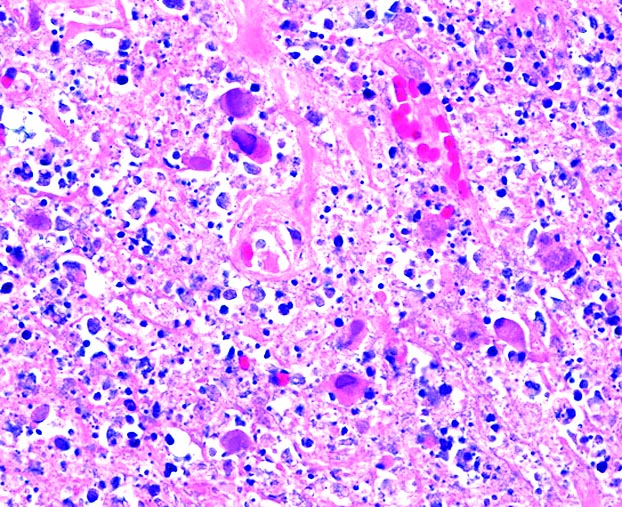

Microscopic (histologic) description

- Early: tiny necrotic foci with neutrophils

- Late: stellate abscesses surrounded by pale epithelioid cells

- Abscesses may merge and sinus tracts may develop

- Macrophages may have organisms within vacuoles

Microscopic (histologic) images

Contributed by Mark R. Wick, M.D.